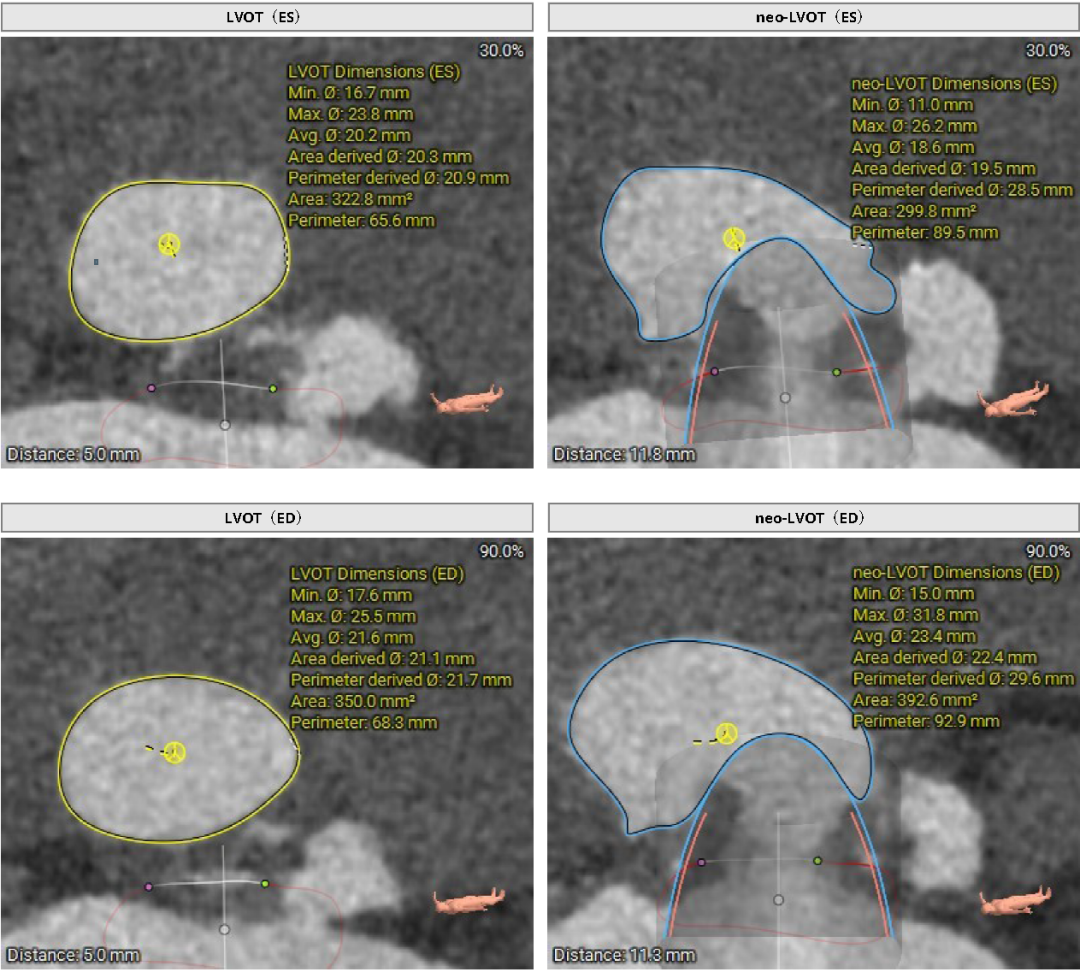

26mm Prizvalve®瓣膜模拟植入,LVOT与瓣架流出端距离为6.9mm。收缩期:LVOT面积322.8mm²,Neo-LVOT面积299.8mm²,舒张期:LVOT面积350.0mm²,Neo-Lvot面积 392.6mm²,综合评估:26mm瓣膜植入后左室流出道梗阻风险低。